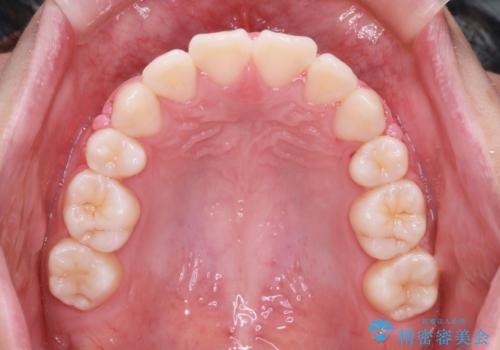

- 前歯の叢生と突出感を主訴に来院されました。

抜歯をしてワイヤー矯正を行いました。

きれいな笑顔になったと喜んでいただけました。

上顎両側小臼歯を抜歯して治療を行い、突出感も大幅に改善しました。